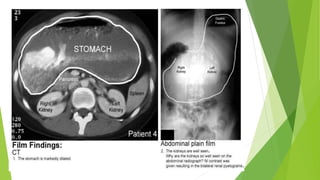

Contrast study demonstrating an

enlarged stomach. The point of

obstruction is visualized at the pyloric-

duodenal junction (string sign).